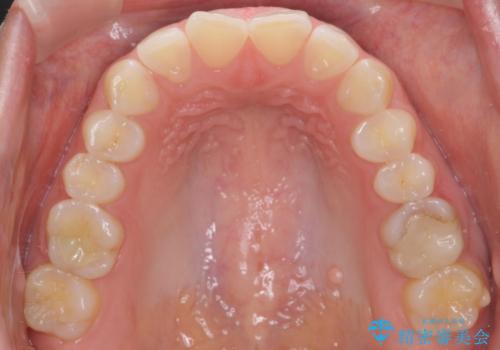

上の前歯のちょっとしたねじれも治療しています。

軽度だったため、部分矯正のコースで短期間で治療しました。

下の歯並びを並べるため、わずかに歯を削合しています。

そうしないと、前に出て上の前歯に強く当たってしまうためです。また、後戻りを防ぐ効果もあります。